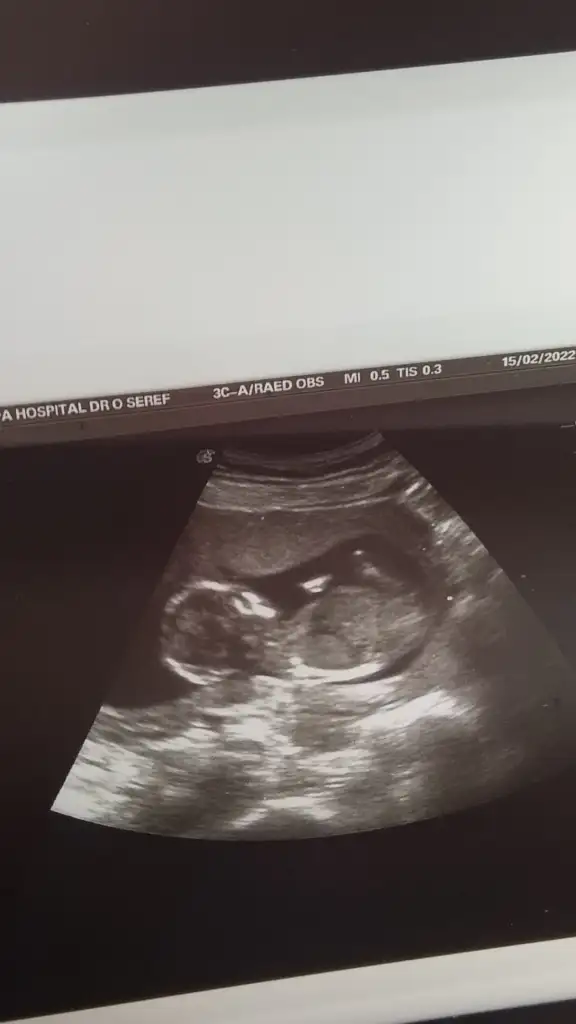

Tesekkurler canmKiz görünüyor

Erkek görünüyor

Beni de yine atladınız sanırım...Ikra meyra Tam 13 haftalığz doktor bır tahminde bulundu ama degısır mı bılemedım bize de bır bakabilir mısınız

Net olmayınca bakmıyorum nubu karışık emin olamadım kız gibi sanki emin değilimIkra meyra banada tahmin yapabilir misin canım?? 12 haftalık

Kiz gibi sanki çok net değil USGBeni de yine atladınız sanırım...Ikra meyra

Doktor erkek demişti ama bakalm artık hayırlısıKiz gibi sanki çok net değil USG